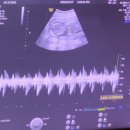

다녀온 후기! ​ 한번 더 기형아 검사에 대해 정리해보자~ 1차 ​ 목덜미 투명대(NT) 측정 (Sequential test) ​ 태아 목덜미 투명대란? ​ 임신 11주에서 13주 6일 초음파 검사 시에 정상적으로 보이는 태아 뒷 목덜미에 체액성분이 고여 있는 공간을 의미합니다. 정상 범위 이상으로 증가된 태아 목덜미 투명대는 다운증후군과...